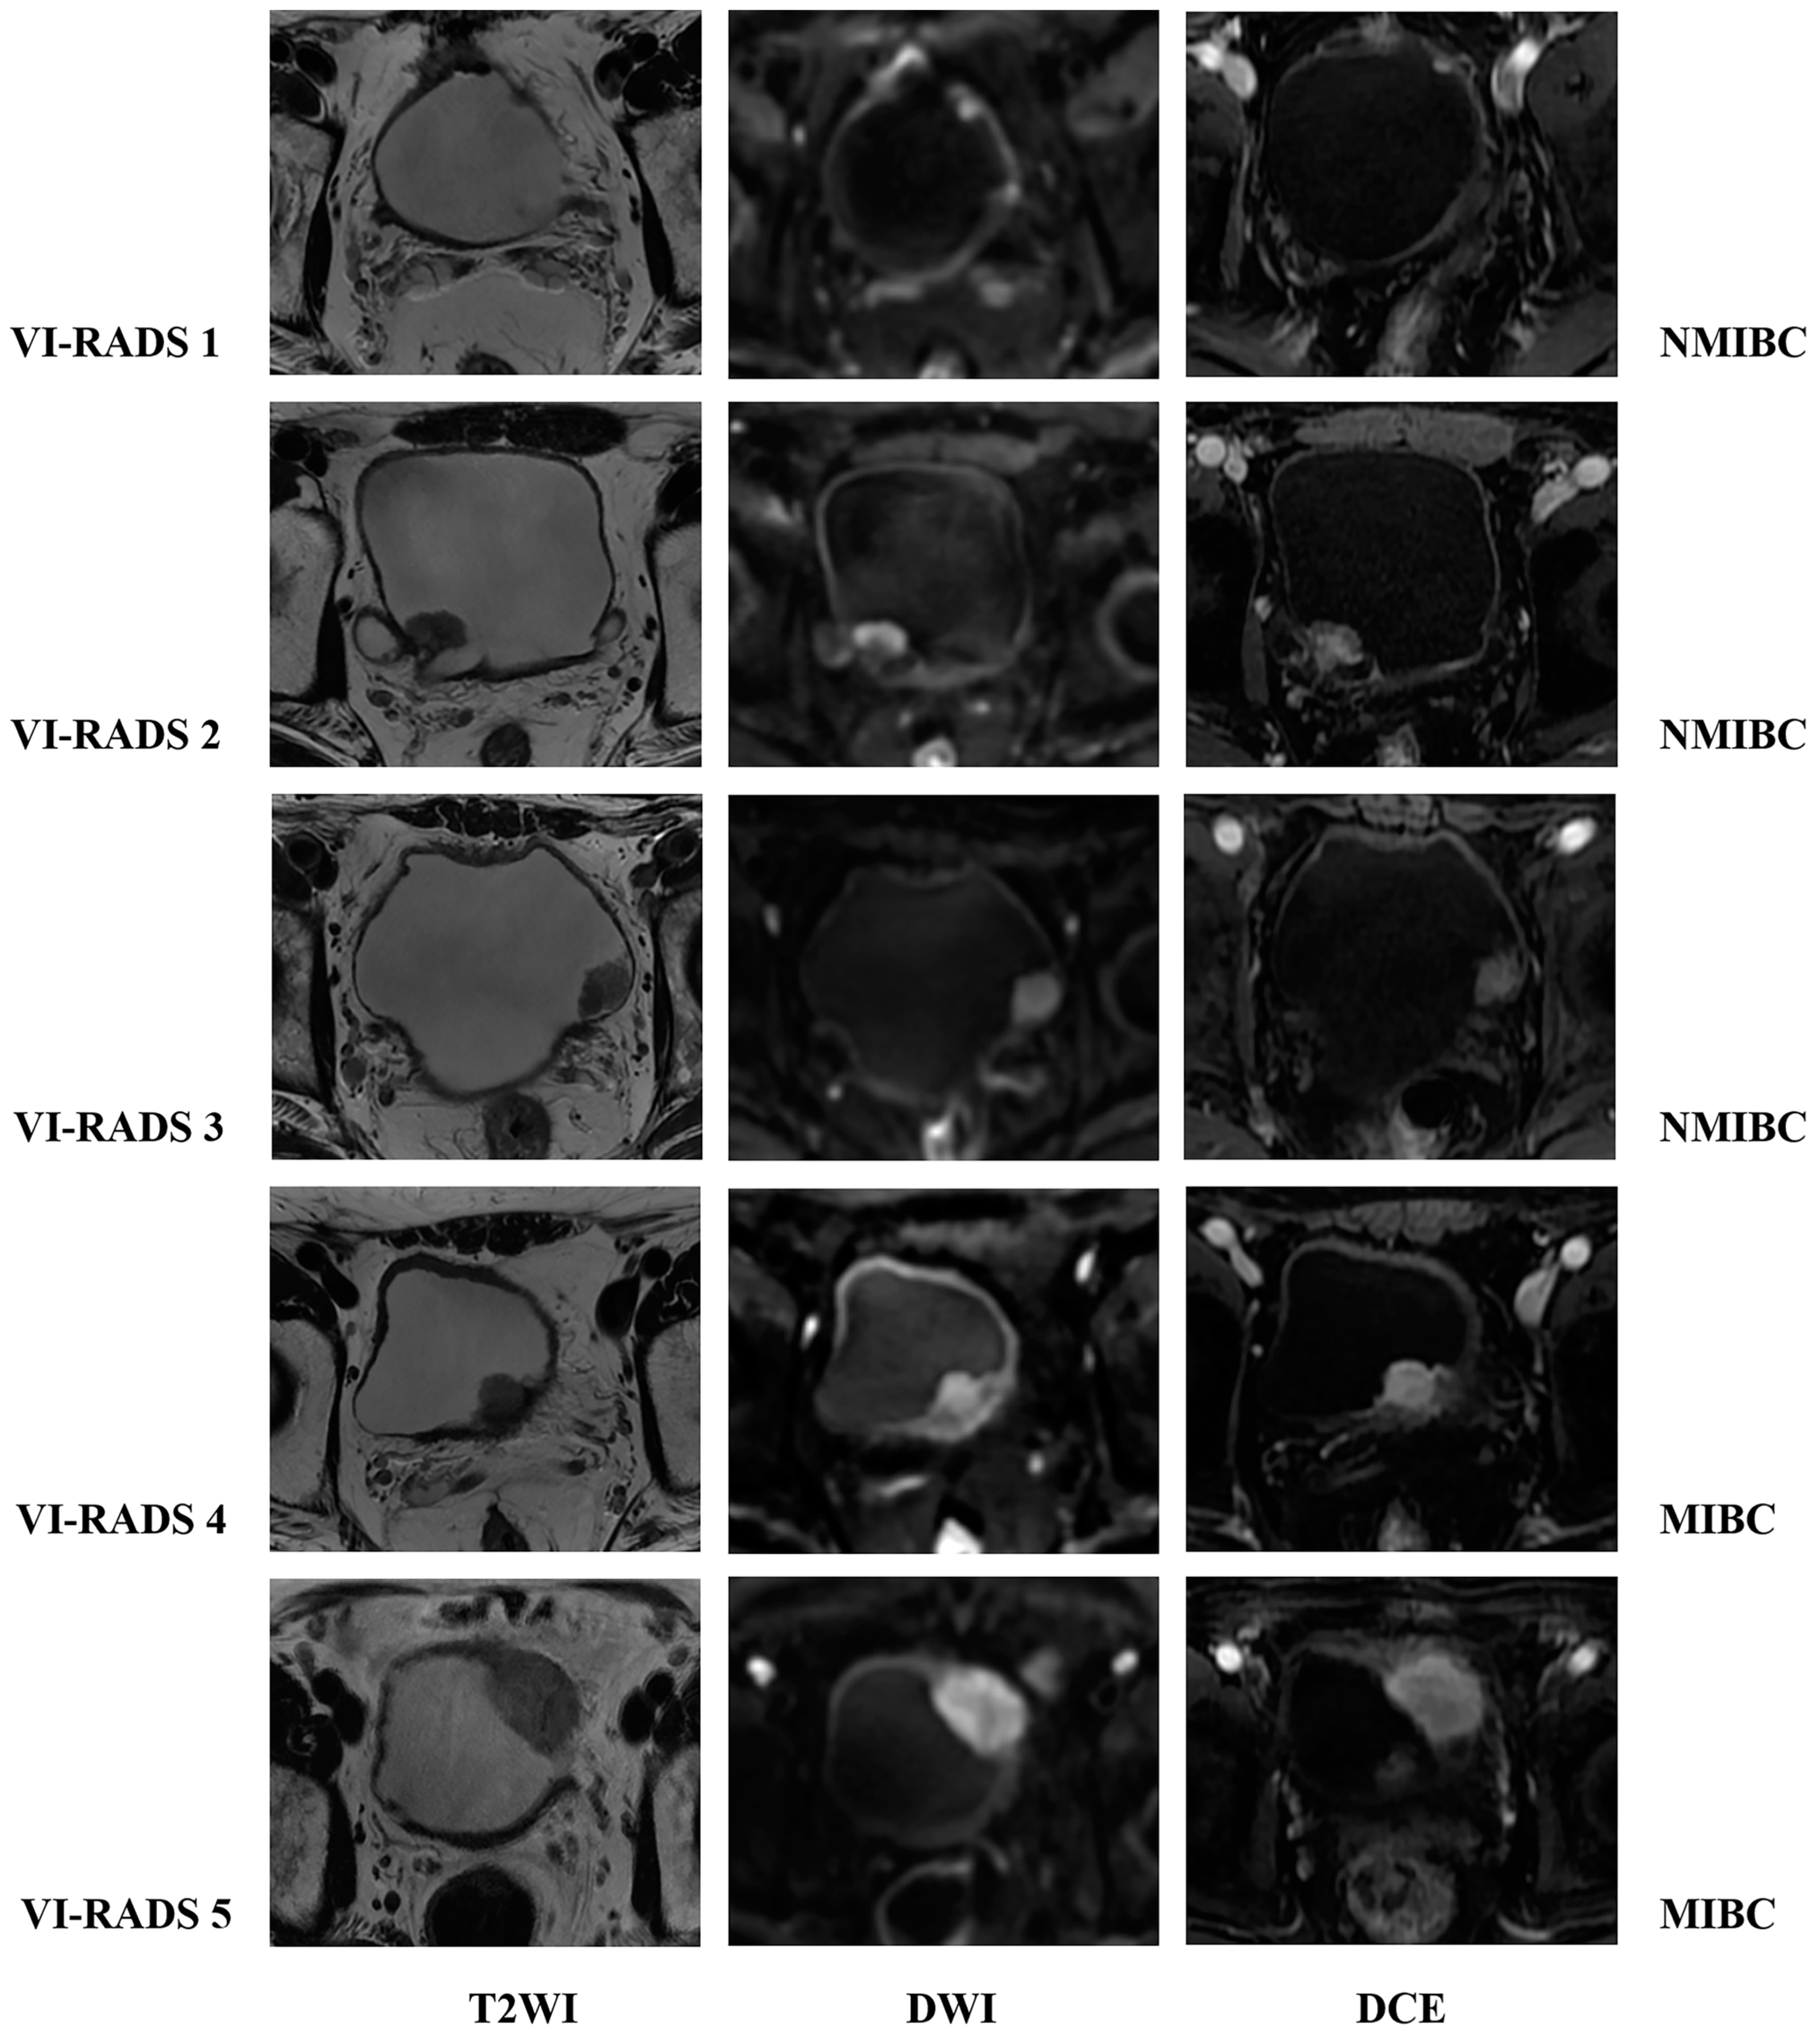

4. The VI-RADS

4.1. The Value of VI-RADS in Evaluating Muscle Invasion in Bladder Cancer